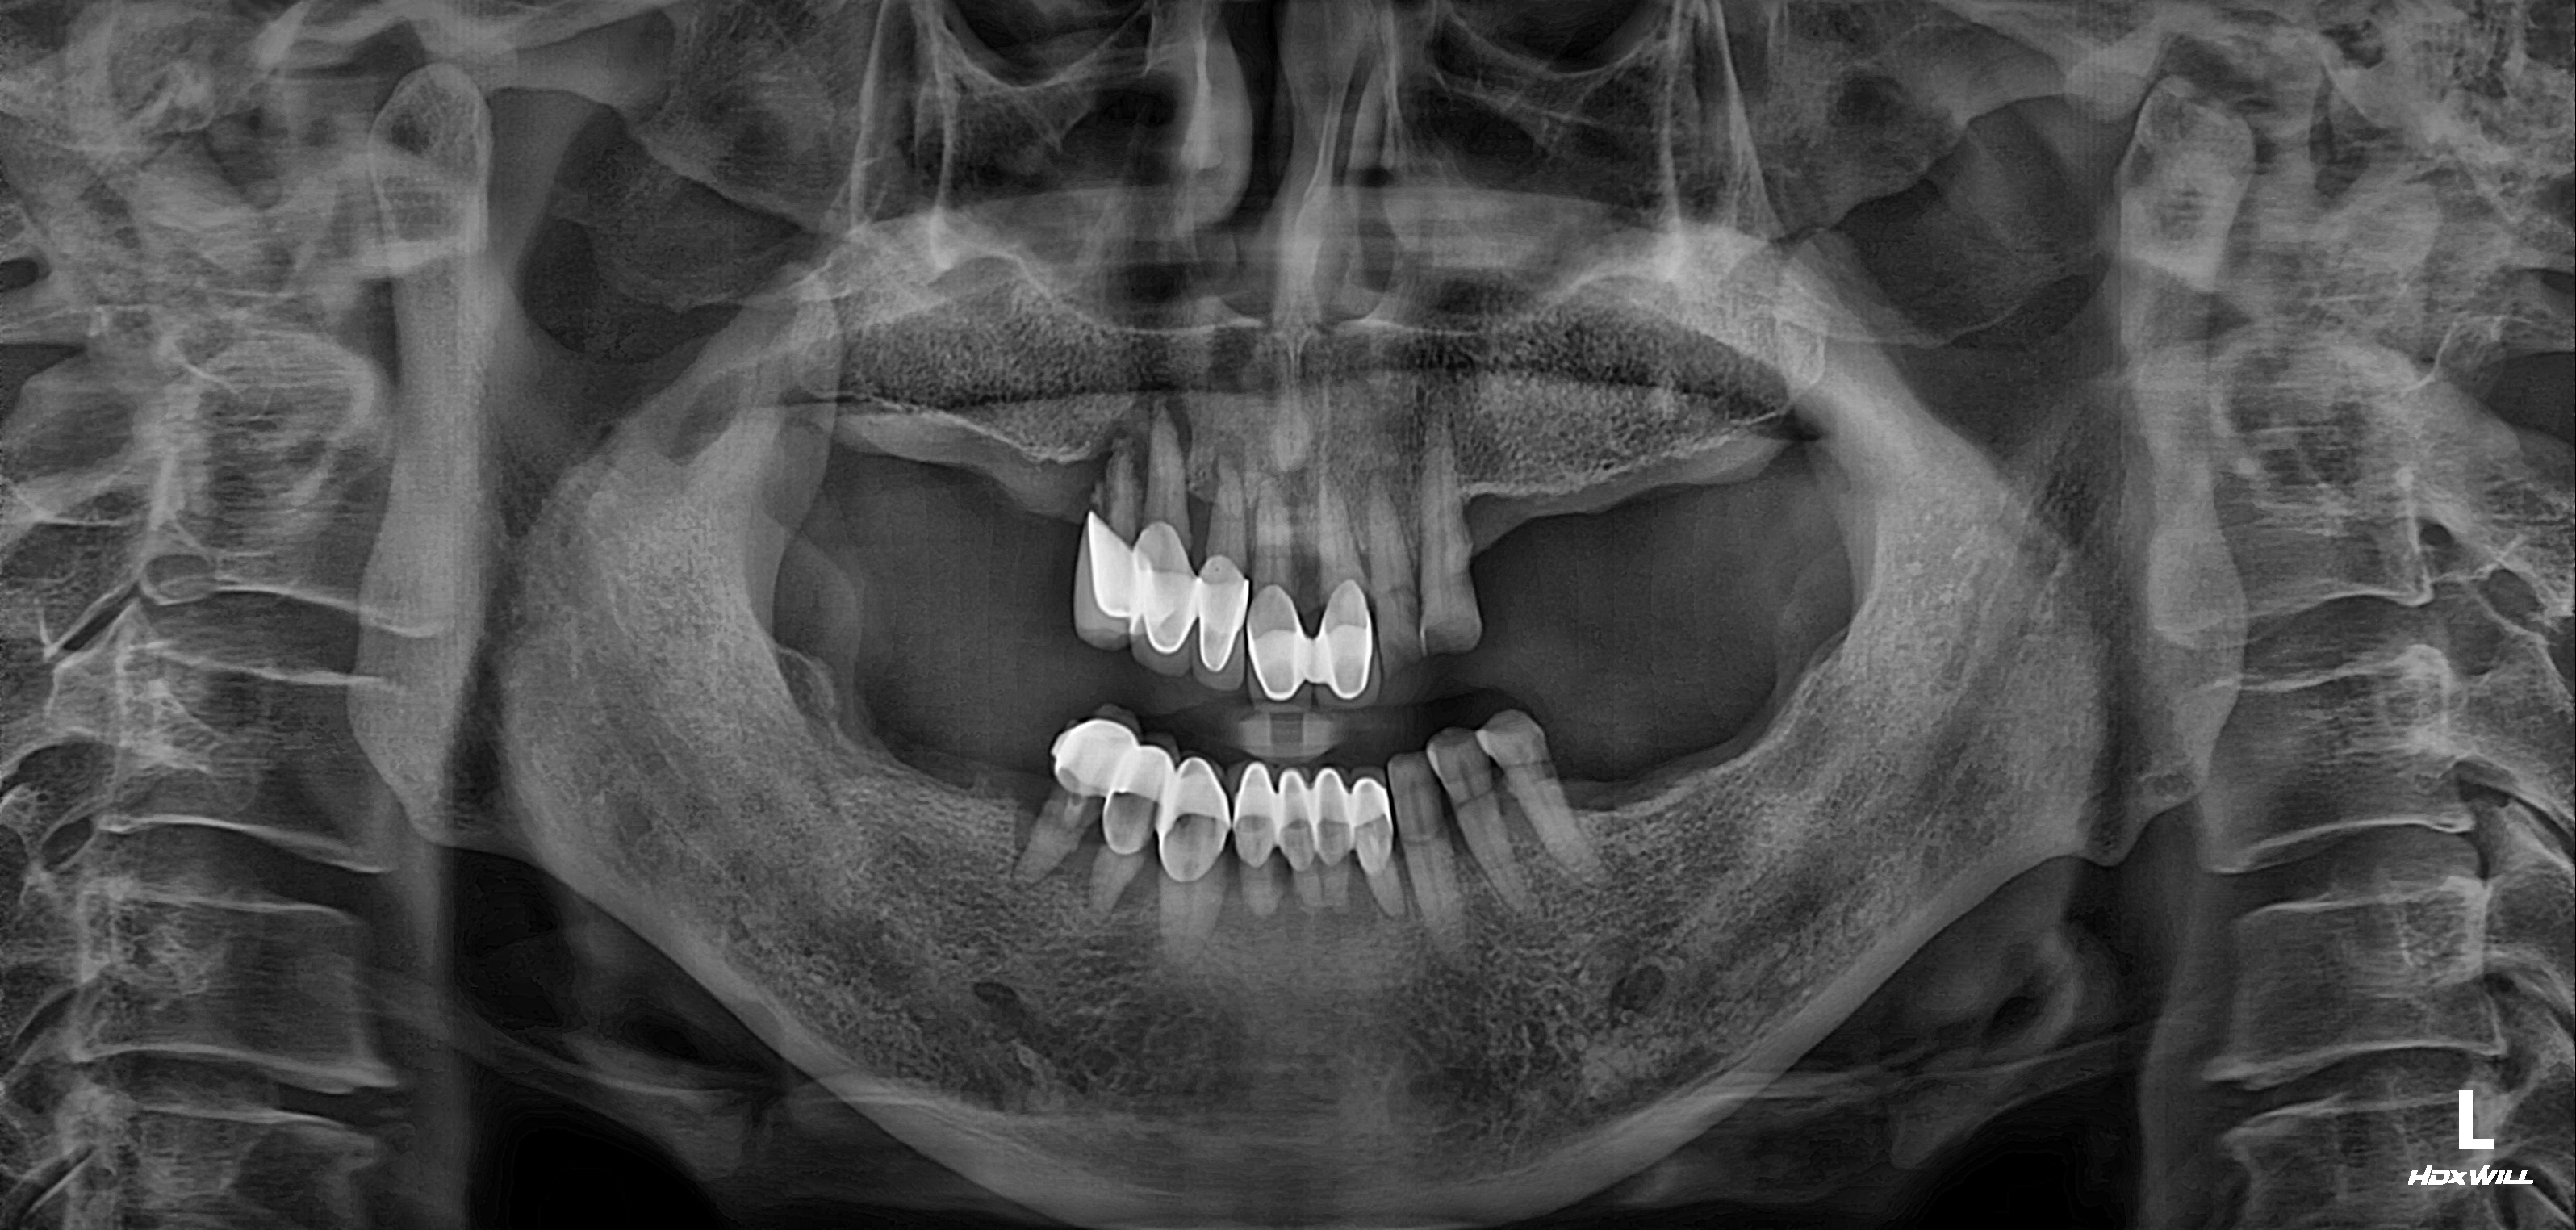

전악 임플란트 식립사례

임플란트